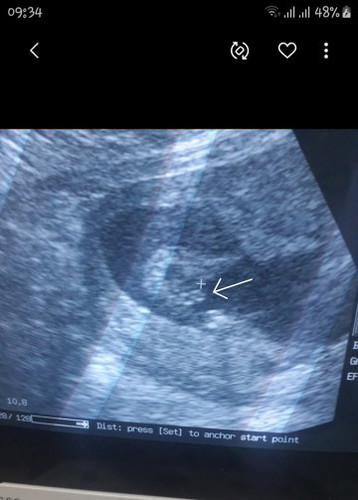

แบบนี้ ผช.ชัวไหมค่ะซาวตอน 15w. คุณหมอบอกน้อง ผช.แม่ๆบ้านอื่นผลซาวลูกชายเป็นแบบไหนกันบ้างค่ะ???

โชว์ปู๋ขนาดนี้ แม่ตั้งชื่อรอได้เลยงับบบ